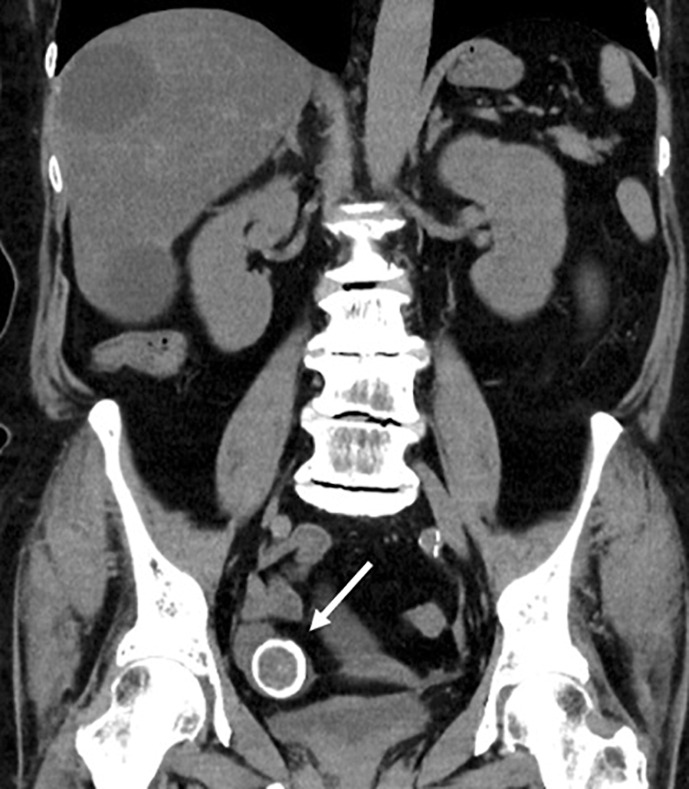

Case presentation: A 69-year-old female presented to the emergency department with nausea, emesis, and abdominal pain. After computed tomography revealed the diagnosis of gallstone ileus, enterolithotomy was performed without postoperative complications. Cholecystectomy and fistula closure were not performed due to inaccessibility to the gallbladder and the high surgical invasion required. Four months later, the patient developed gallstone ileus again. A second enterolithotomy was performed immediately, resulting in a favorable outcome without complications.